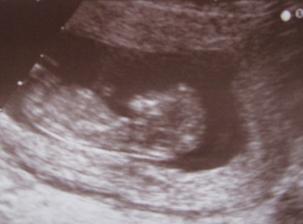

17.10. vyšetření ve 12.týdnu, první fotečka, vše v pořádku, HURÁ